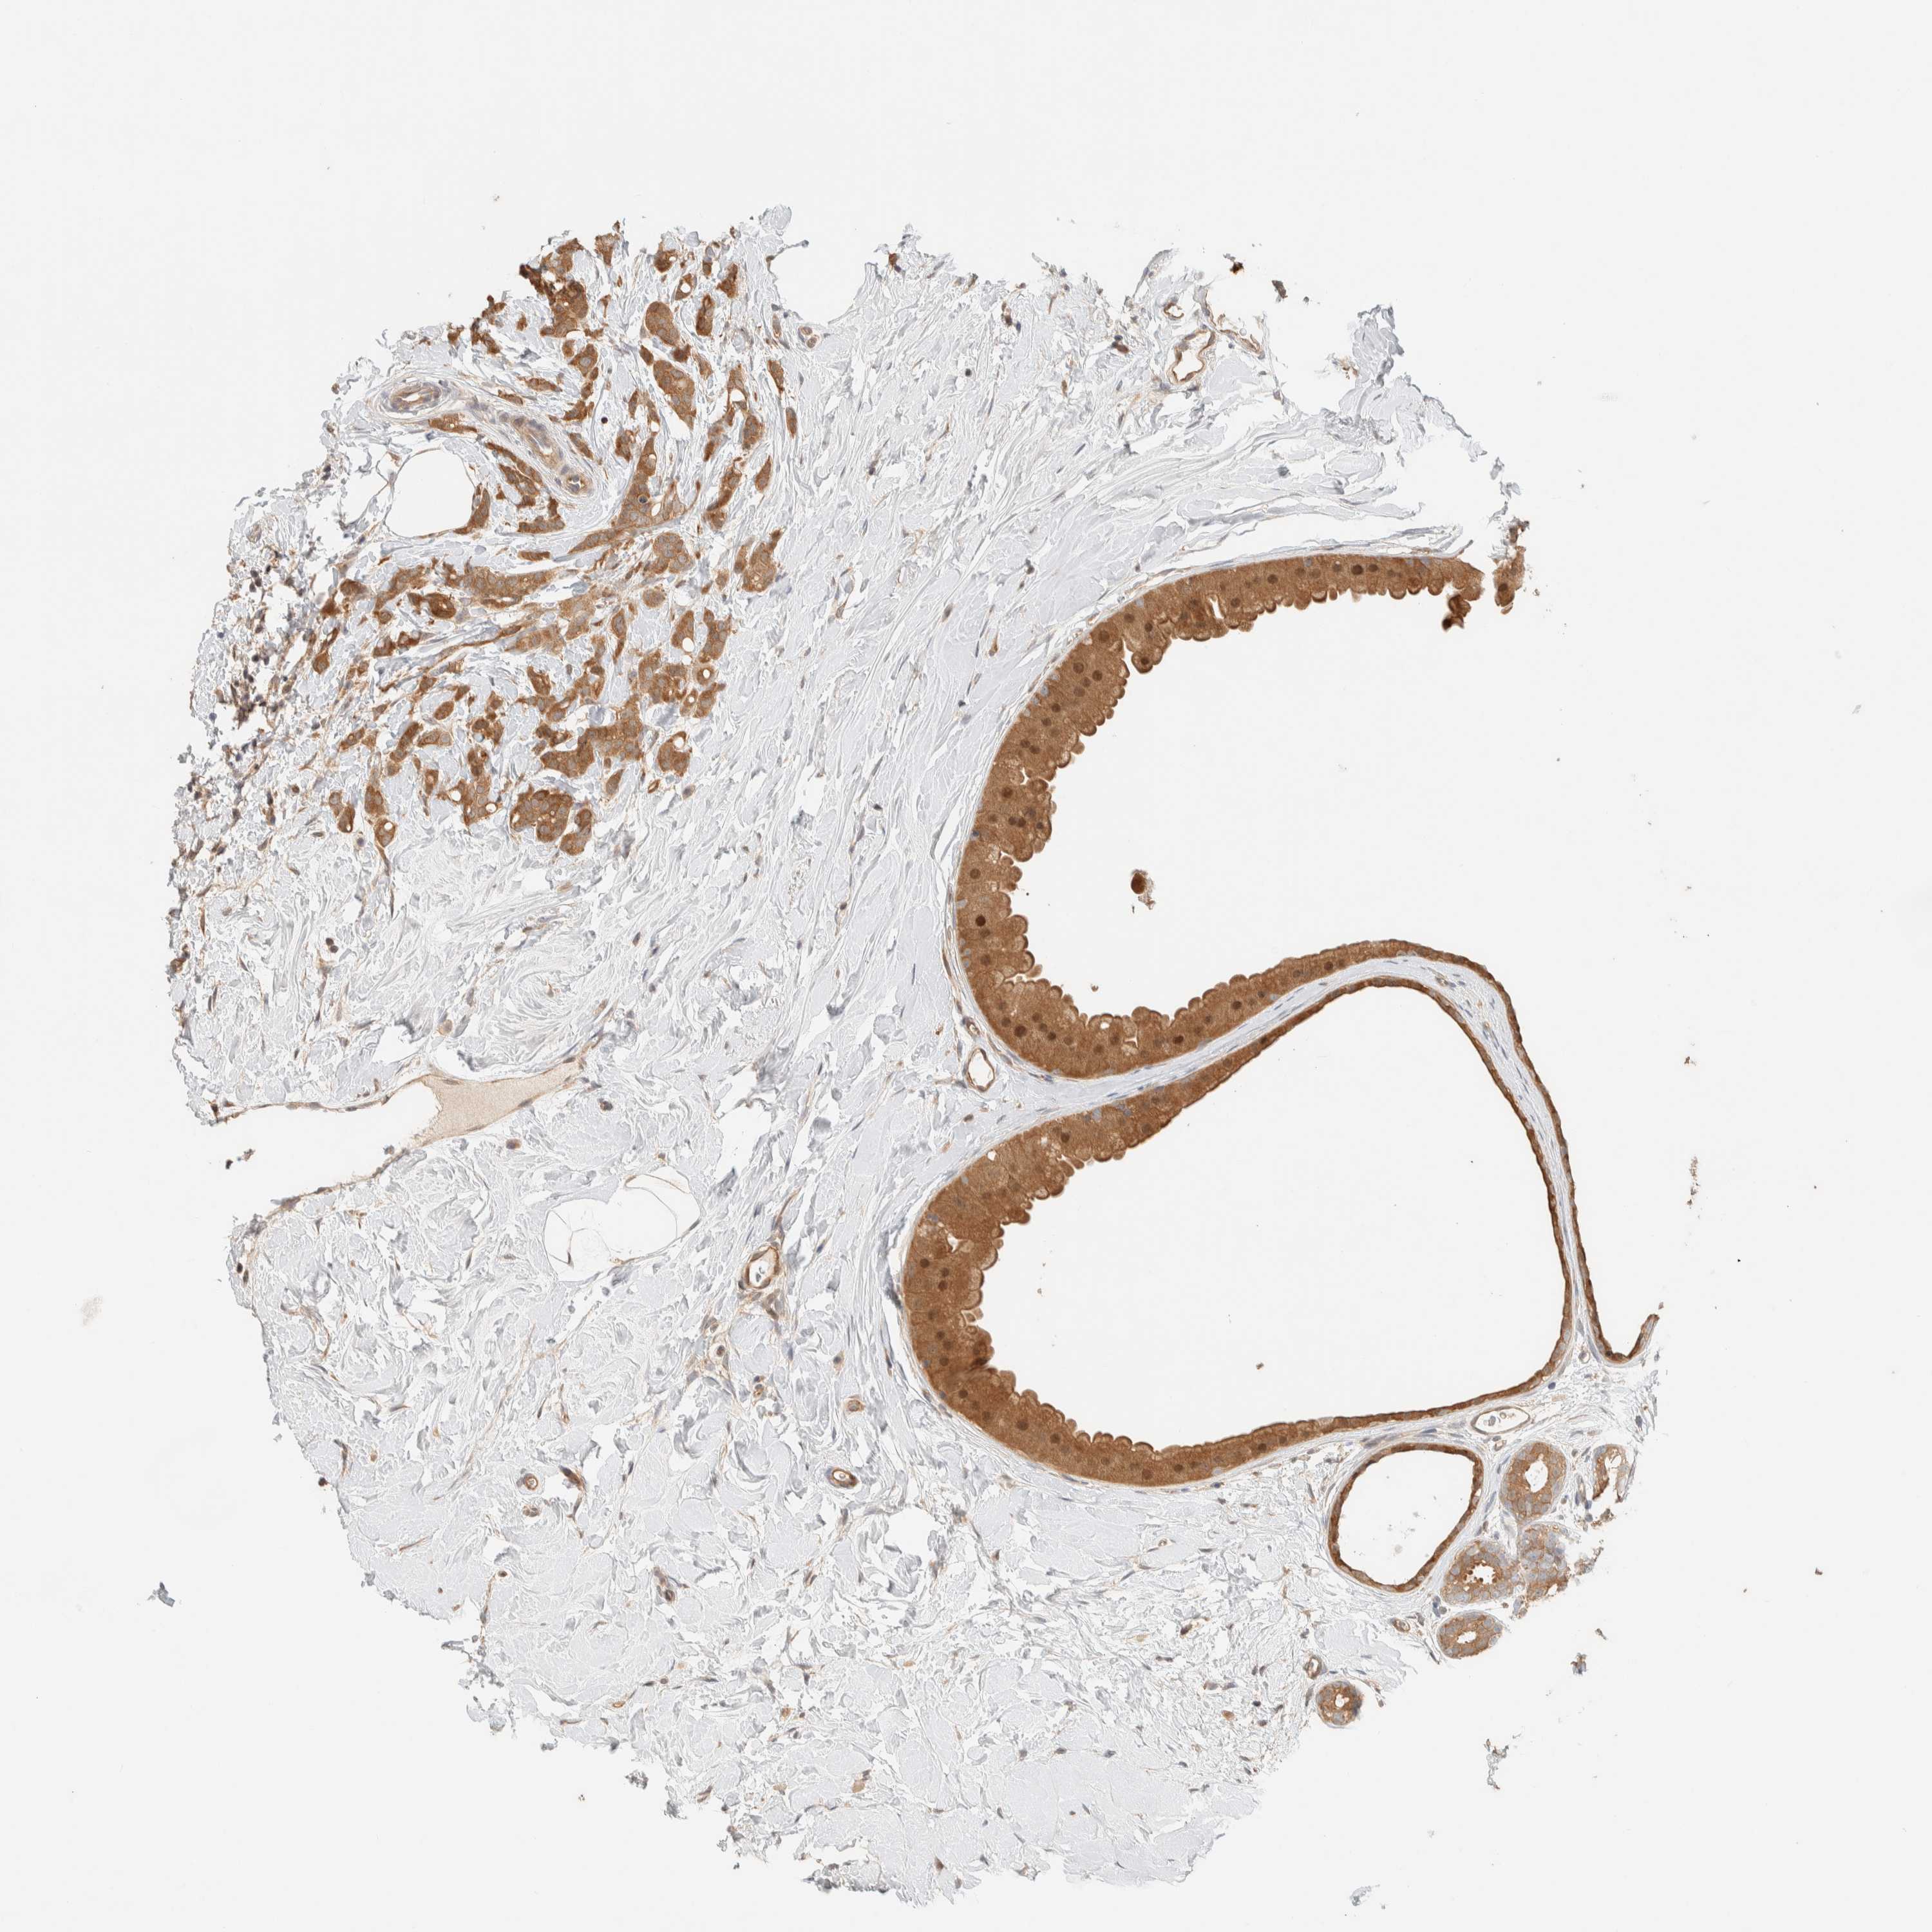

BRCA TCGA BRCA VALIDATION PROTEIN EXPRESSION